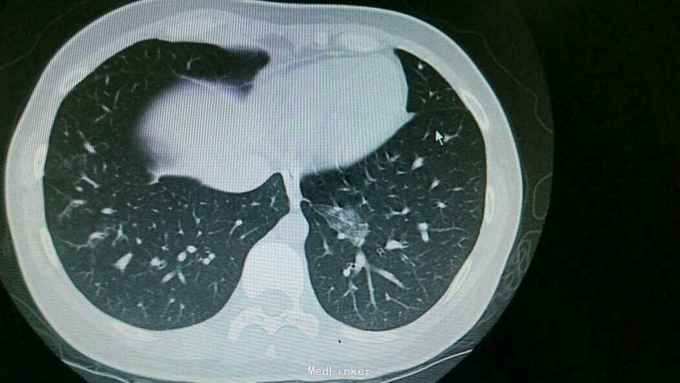

查体:双肺呼吸音粗,右肺可闻及湿罗音, 余无特殊 辅查:血常规示中性粒细胞稍高。胸片:右上肺野炎性病变。肺炎支原体抗体滴度1:640。胸部CT:双肺炎症。

诊断:支原体肺炎。 治疗,予以阿奇霉素抗感染,止咳化痰等处理。复查胸片提示炎症较前好转。